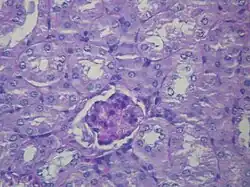

| Microscopic image of diabetic glomerulosclerosis, the main cause of nephrotic syndrome in adults. | |

- Focal segmental glomerulosclerosis (FSGS): is the most common cause of nephrotic syndrome in adults.[22] It is characterized by the appearance of tissue scarring in the glomeruli. The term focal is used as some of the glomeruli have scars, while others appear intact; the term segmental refers to the fact that only part of the glomerulus is damaged.

Secondary causes of nephrotic syndrome have the same histologic patterns as the primary causes, though they may exhibit some differences suggesting a secondary cause, such as inclusion bodies.[24] They are usually described by the underlying cause, such as:

- Diabetic nephropathy: is a complication that occurs in some diabetics. Excess blood sugar accumulates in the kidneys, causing them to become inflamed and unable to carry out their normal function. This leads to the leakage of proteins into the urine.